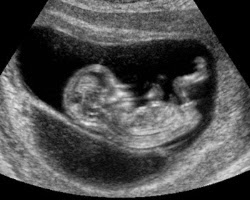

The second ultrasound that is done midway during a pregnancy is called a 'level 2 ultrasound' and can give a detailed image of the growing fetus. The actual image that is projected from the ultrasound and the image a mother takes home to show her friends and family is called a Sonogram. The medical reasoning behind these freeze-framed images is because babies this late into trimester move a lot so the physician takes these snapshots to more accurately check that the baby is developing normally.

First Trimester:

![]() |

| Week 9 |